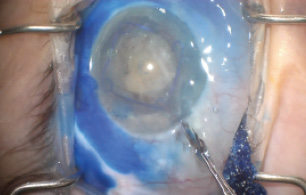

Complex Cataract Extraction With Transconjunctival Bleb Revision

The vision in his better-seeing eye had declined to light perception, and he had a grade 3 flat anterior chamber, a white cataract, a large bleb, and an IOP of 7 mm Hg. B-scan ultrasonography did not demonstrate any choroidal effusion. The decision-making at this point was clear, and I recommended that we proceed immediately with cataract extraction and bleb revision, which we did (see Watch It Now).